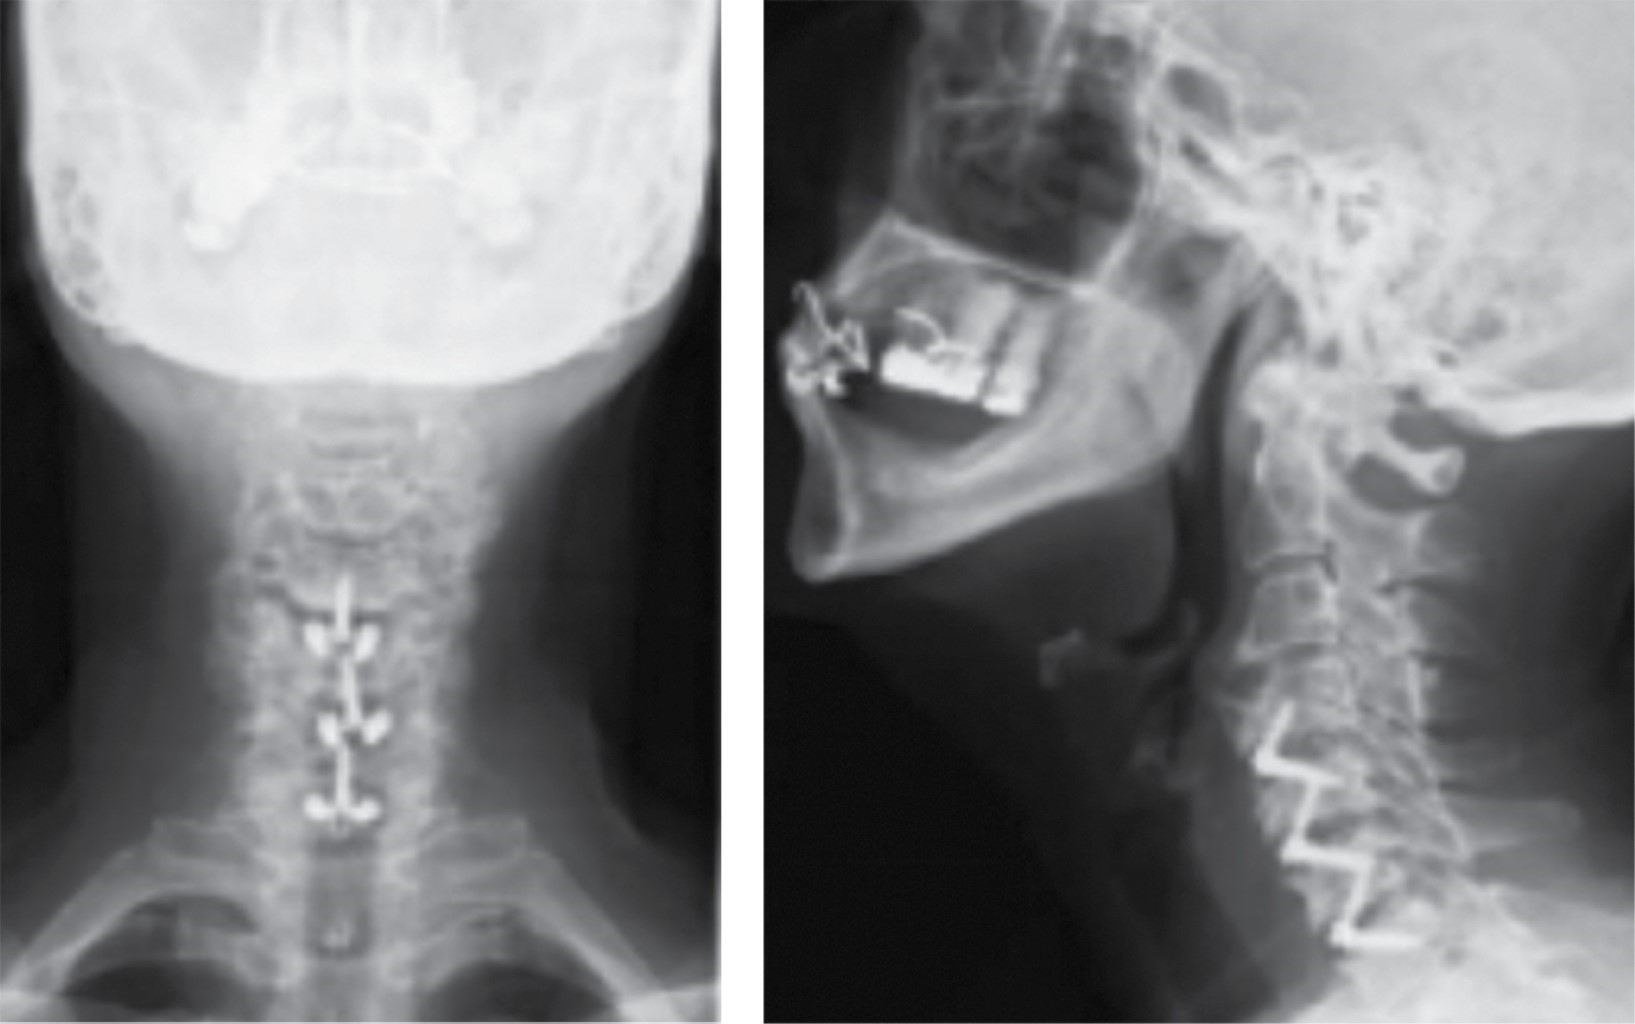

En las distintas revisiones los pacientes mostraron una mejoría tanto de la lordosis cervical como de la altura discal (Figura 1) en comparación con los resultados preoperatorios (Figura 2). Se encontraron estudios realizados con placa e injerto, mejoría en el ángulo de Cobb y en la altura intersomática (p = 0.038 y p = 0.0004, respectivamente).10 En estudios que evaluaron el resultado radiográfico con relación a la lordosis global no hubo diferencia estadísticamente significativa entre usar placa-injerto, placa-caja o caja de PEEK, (p = 0.003, p = 0.006 y p = 0.001, respectivamente), lo cual nos permite efectuar un abordaje menos invasivo con resultados satisfactorios. Shan-Jin Wang y colaboradores demostraron en su estudio realizado en cuatro niveles con cajas de PEEK, que el ángulo de Cobb y la altura intersomática mejoraron de manera postoperatoria con una significancia clínica con un valor de p = 0.019 y p ≤ 0.01, respectivamente,11 lo que demuestra que se puede obtener un resultado radiográfico satisfactorio independientemente de la cantidad de niveles operados.

En el Instituto Nacional de Rehabilitación "Luis Guillermo Ibarra Ibarra" (INRLGII) actualmente se realiza discectomía y fusión cervical anterior. Siendo éste un centro nacional de referencia y tomando en cuenta la bibliografía consultada, en la cual aún se debaten ciertas técnicas y material empleado dependiendo de los niveles intervenidos, se decidió dirigir un estudio en el cual se realizó descompresión anterior en tres niveles y fijación con cajas autobloqueantes en columna cervical. Se estudiaron en un periodo de cinco años (2014-2018) con el protocolo quirúrgico del servicio (Figura 3), obteniendo un total de 21 pacientes con diagnóstico de conducto cervical estrecho con o sin mielopatía, tomando en cuenta parámetros clínicos (EVA, JOA, Nurick, IDC, SF-36) y radiográficos (lordosis cervical, altura del cuerpo vertebral y altura intersomática), obteniendo resultados significativos en la muestra estudiada. En el Servicio de Cirugía de Columna del INRLGII existe en la actualidad una línea de investigación en patología degenerativa de columna cervical que busca un equilibrio entre la mejoría clínica y radiográfica que minimice las complicaciones.

Figura 1

Figura 2

Figura 3